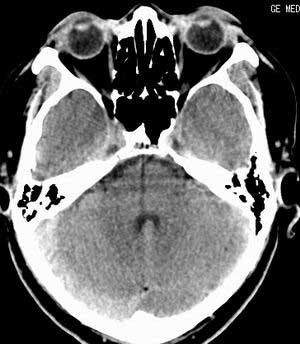

患者男,58岁。耳爆震伤后耳聋2年余,而后双耳道肿胀,间断性流脓。近一月来头痛、恶心、呕吐,右眼红痛,不能入眠。

在平扫时,见右侧枕骨下方小脑半球表面带状模糊稍高密度影,考虑为耳源性脑内感染。

平扫右侧岩骨与枕骨交角内侧脑质内见淡片状密度增高影,内缘清晰。增强图象上未见明显显示。

右枕颅骨内板下高密度应该是窦的变异,和其症状应该无关,根据病史另找原因吧。[em16]

条状高密度为小脑幕吧

条状高密度为小脑幕

横窦乙状窦。

增强的横窦乙状窦。